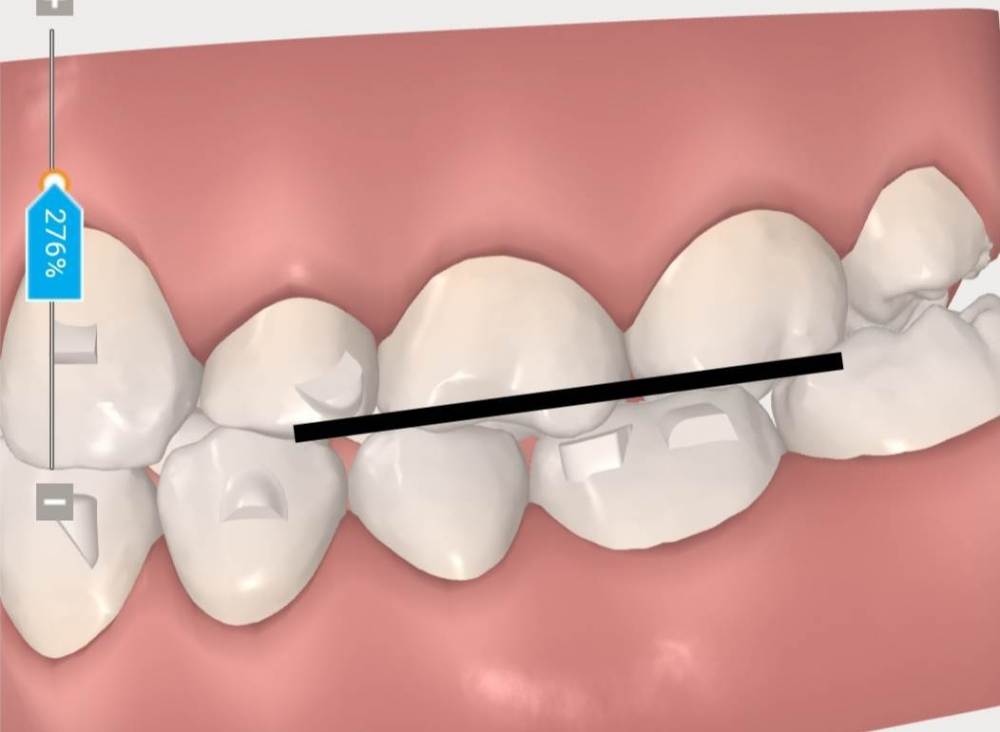

АнтонТЛТ Опубликовано 5 января, 2022 Поделиться Опубликовано 5 января, 2022 Задние бугры верхнего левого первого моляра находятся ниже уровня где они должны быть, это связано с выдвижением зуба из-за длительного наклона нижнего левого первого моляра. Так же этот верхний зуб находится в более нёбном положении относительно соседних зубов. Ссылка на комментарий

АнтонТЛТ Опубликовано 5 января, 2022 Поделиться Опубликовано 5 января, 2022 Правый верхний первый моляр так же имеет наклон задних бугров, связано это скорее всего с тем, что нижний правый первый моляр долго находился в разрушенном состоянии и верхний зуб выдвинулся. Нужно поменять наклон верхнего зуба и потом сделать коронку на нижнем. Ссылка на комментарий

АнтонТЛТ Опубликовано 5 января, 2022 Поделиться Опубликовано 5 января, 2022 Эти выдвинувшиеся верхние зубы создают блок в движении нижней челюсти. Из-за этого блока нижняя челюсть движется по неправильной траектории и смещается в сторону. Что в дальнейшем может привести к проблемам в височно- нижнечелюстных суставах. Перед ортодонтическим лечением нужно удалить зубы мудрости и вылечить все зубы где есть кариес. Так же разобраться с нижним правым первым моляром, если там есть проблемы с корнями. 1 Ссылка на комментарий